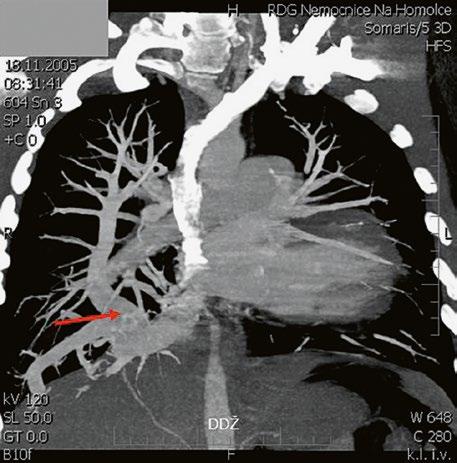

Supravalvární pulmonální stenóza a stenózy větví plicnice bývají součástí komplexních VSV (např. Fallotovy tetralogie) nebo syndromů (Williamsův syndrom, syndrom Noonanové, syndrom vrozené rubeoly, Alagillův syndrom aj.) (Obr. 45.39). Získané stenózy větví plicnice, ale i úplný uzávěr větve plicnice můžeme vidět po spojkových operacích podle BlalockaTaussigové (Obr. 45.40, Obr. 45.41). Pro zobrazení supravalvárních a periferních stenóz plicnice je optimální CT angiografie (Obr. 45.40, Obr. 45.41, Obr. 45.42, Obr. 45.43).

Obr. 45.40 CT angiografie, 8mm stenóza a deformace levé větve plicnice (šipka) po spojkové operaci podle BlalockaTaussigové v dětství LPA – levá větev plicnice, PA – kmen plicnice, RPA – pravá větev plicnice

Obr. 45.41 Uzávěr levé větve plicnice jako následek provedené spojky podle BlalockaTaussigové v dětství, CT angiografie

Obr. 45.43 CT angiografie, šipkou označena významná odstupová stenóza levé větve plicnice (LPA), lehčí stenóza odstupu pravé větve plicnice (RPA), kalcifikace v oblasti pulmonální chlopně